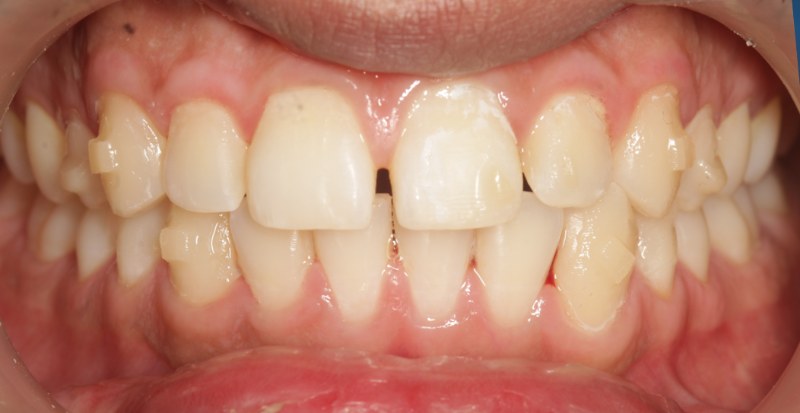

After invisalign treatment

Before After

Invisalign

Clear aligner orthodontics

Crowding and a midline gap corrected with a series of clear aligners — no metal brackets, fully removable for daily life.